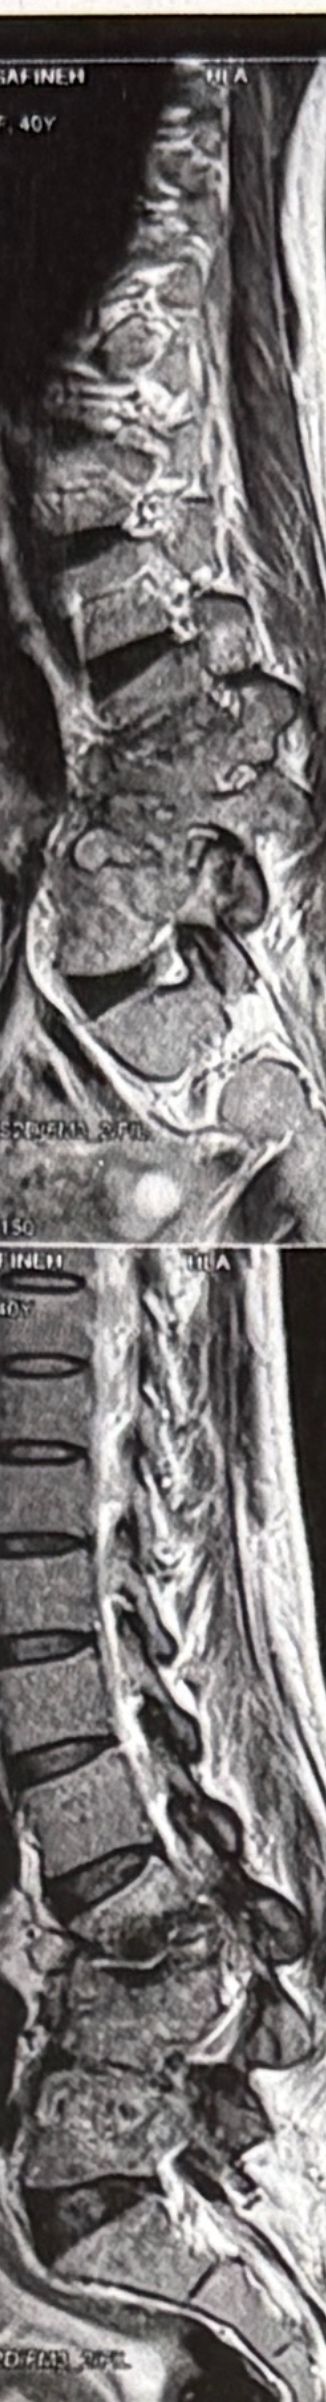

41 years old man presented to my clinic in October 2023 with acute and sever R neck pain with radicular pain to his R upper extremity along C6 dematom since 2 weeks ago. Examination didn’t show any upper motor signs. Was suggested urgent surgery

I ordered EMG/ NCV : showed mild R C6, C7 irritation without any active axonal loss

In his MRI was reported R. para R. IVF Massive extrusion. I decided to control his pain and manage this patient with reevaluation of patient every other session. For 5 sessions i just used acupuncture and laser and IFC and mild adjustments to his R. T3-T7 and mild arthosteem to above and below involved segment. Cervical adjustment considered contraindicated for this patient. From session 6th- 8th i started to use mild/gentle cervical decompression. He used soft cervical collar all the time. His pain decreased by 80 percent

I gave him cervical traction pump to be used 3-5 times per day at home for the next 3 months and i released the patient. He was evaluated every week once for one month and after that every 2 weeks. After 3 month I repeated MRI. Size of the herniated disc was reduced greater than 50 percent. Asked him to do another mri in 6 months

In general: Precise selection of the patients, examination,diagnosis, plan of management, reevaluation and treatment can be done by doctors of chiropractic for the patients with spinal disc herniation and stenosis Moreover giving reasonable time to these kind of patients under direct supervision by their chiropractic doctors can prevent unnecessary surgery. Proper selection of these kind of patients is another important fact that can be done precisely by chiropractors.

MRIs before and after proper management of this patient: